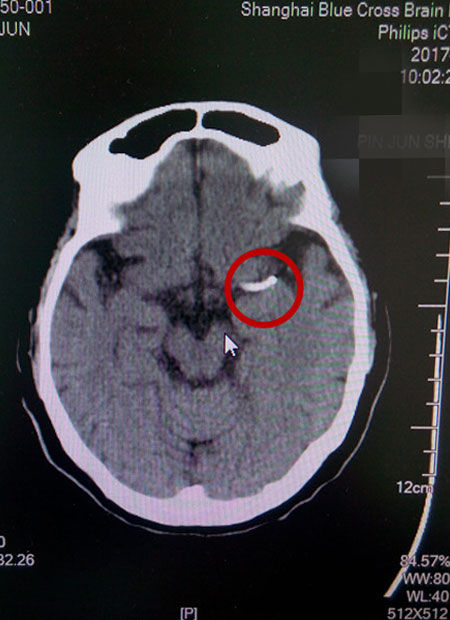

术后CT影像:支架成功置入

就这样,这台DSA手术又一次获得了成功,术后CT复查无出血,患者恢复情况良好,这才出现了本文开头的感人一幕。原本大面积脑梗、病情凶险的的盛阿姨在李主任和团队的努力下,通过DSA球囊扩张支架置入术,平安度过了生命中的一个转折点。随后,在不到一个月的时间里,她的语言功能已逐渐恢复,四肢肌力已经接近正常水平,目前正在积极接受康复治疗中。